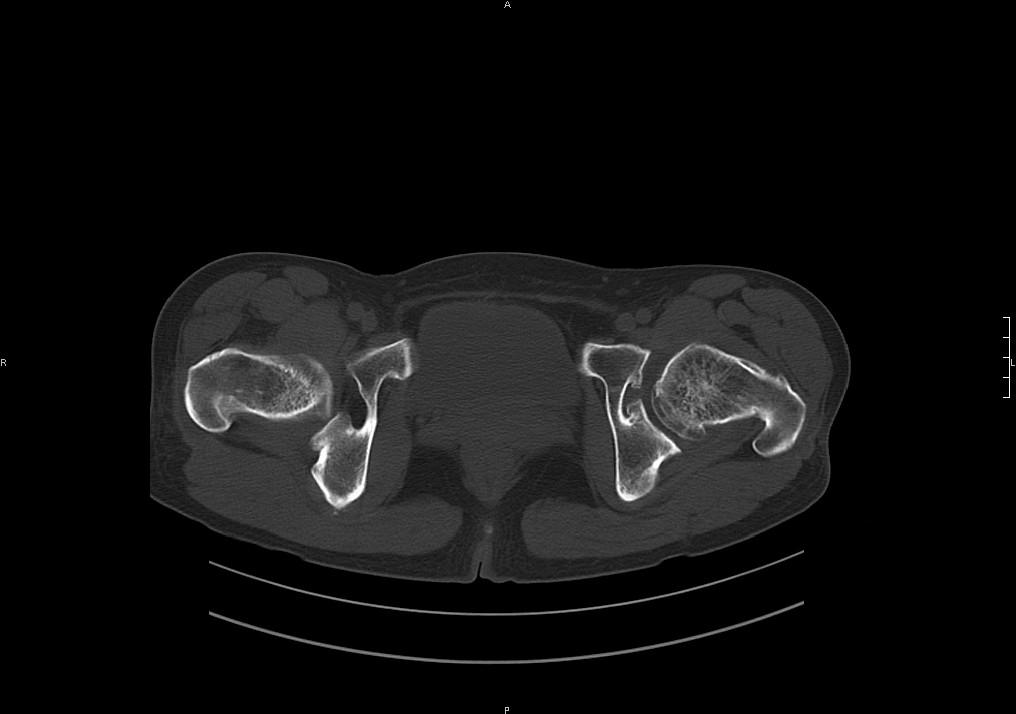

标题: CT19780左髋关节疼痛伴跛行1年,加重1个月。无菌性坏死? [打印本页]

标题: CT19780左髋关节疼痛伴跛行1年,加重1个月。无菌性坏死?

左髋关节内内可见关节鼠及滑囊积液.

考虑为滑膜骨软骨瘤病.

滑膜增厚钙化,关节鼠及滑囊积液,髋臼增生。考虑骨性关节病

髋臼平浅,股骨头覆盖率减小,考虑双侧髋关节发育不良伴退行性变。

股骨颈陈旧性骨折

髋关节退行性骨关节病

滑膜增厚钙化,关节鼠及滑囊积液,髋臼增生。考虑骨性关节病。